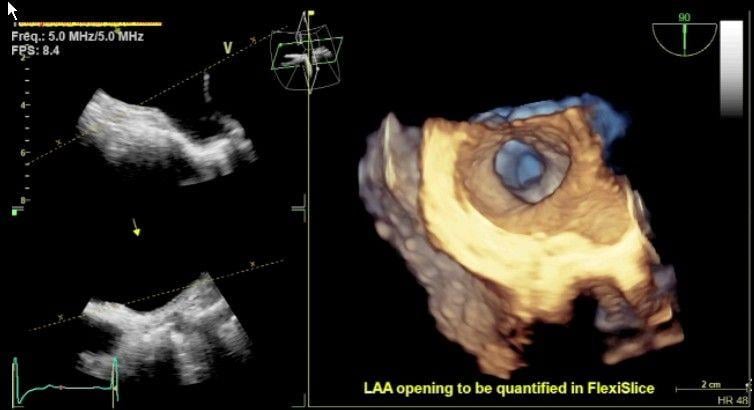

GE Healthcare's 3-D/4-D echo system, showing implantation of ASD occluder in a septal wall defect. This type of virtual surgical view enables several new types of procedures that otherwise would be difficult to perform.

Transesophageal echocardiography (TEE) is quickly establishing itself as an essential tool in the interventional cardiologist’s daily toolbox. An alternative to the more traditional transthoracic echo, TEE provides higher quality images due to the esophagus’ location directly behind the heart. With the introduction of 3-D/4-D TEE, the technology has become a primary imaging modality to guide new, complex transcatheter structural heart procedures, including transcatheter aortic valve repair (TAVR), MitraClip, transcatheter mitral valve replacements (TMVR), left atrial appendage (LAA) occlusions, and septal defect closures.

For the most part, though, 3-D visualization has gained widespread acceptance, mainly because it provides a “surgeon’s view” of the anatomy that is easier for most cardiologists to interpret. “The technology for 3-D has gotten less cumbersome,” said Khandheria, making it more accessible for more personnel with less specialized training required.